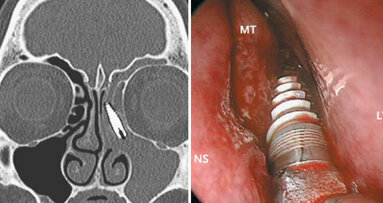

«La grave ipoacusia e l’anacusia con la conseguente dislalia audiogena – dice – sono sempre state oggetto di interesse da parte dei ricercatori. Dalla lettura labiale, passando per le protesi auricolari si è arrivati agli impianti cocleari, i quali hanno radicalmente cambiato la qualità di vita dei pazienti portatori di sordità gravi o profonde. Come è noto l’impianto cocleare stimola elettronicamente le fibre nervose nell’orecchio interno permettendo all’individuo la percezione dei suoni. La maggior parte degli utilizzatori può sentire la musica o partecipare attivamente a conversazioni, anche in situazioni difficili di ascolto. Gli impianti cocleari – continua – sono utilizzati con successo in oltre novanta Paesi in tutto il mondo, negli adulti e in età pediatrica, risultando efficaci sia in casi di sordità pre-linguale sia post-linguale».

«L’impianto cocleare è particolarmente indicato in giovane età per permettere un regolare sviluppo del linguaggio, inoltre la ricerca ha dimostrato che i migliori risultati si ottengono nei bambini impiantati precocemente. I bambini più grandi e gli adulti ipoacusici post-linguali hanno maggiore giovamento con la riabilitazione uditiva funzionale mediante impianto cocleare piuttosto che con la protesizzazione acustica. Un lungo periodo di perdita uditiva profonda può limitare i vantaggi di un impianto cocleare».

«Fatte queste doverose premesse relativamente all’indiscutibile significato riabilitativo espresso dall’impianto cocleare – osserva ancora Bongioannini – , restano indubbiamente da considerare le problematiche inerenti l’invasività dell’intervento chirurgico necessario (anche se al presente codificato secondo parametri che si avvicinano al microtraumatismo) e naturalmente ai costi. Sotto questo punto di vista lo studio condotto da J. Williams, L. Stone-Roy e J.J. Moritz a Fort Collins (Colorado, USA) presenta aspetti molto interessanti, specialmente nei casi in cui il paziente non possa essere candidato per vari motivi ad un impianto cocleare. In questa fase preliminare ritengo che l’attenzione dei ricercatori vada effettivamente concentrata prima di tutto sulla “mappatura” qualitativa e quantitativa dei recettori degli impulsi elettrici a livello della lingua, non essendoci una stimolazione diretta delle strutture neurosensoriali uditive deputate come avviene nell’impianto cocleare».